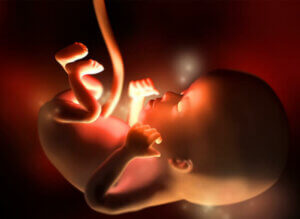

오늘은 임신 12주차의 특징에 대해 알아보자. 임신 12주차에 태아의 키는 약 5~6cm, 몸무게는 약 8~14g이다. 태아의 심장은 분당 160회로 매우 강하게 뛰고 움직임도 증가하기 시작한다. 하지만 태동은 아직 눈에 띄는 정도는 아니다.

태아의 크기는 이 시점에서 자두 또는 패션프루트 정도 크기다. 사실 지난 주차부터 현재까지 아기는 약 15% 성장했다. 사지가 이미 형성되었고 장기가 빠르게 성숙하기 시작하며 지금까지 탯줄 기저부에 연결되었던 내장도 복강으로 이동한다.

또한, 머리는 둥근 모양을 갖게 된다. 입을 여닫을 수 있으며 귀도 제자리에 있다. 성대와 손톱도 형성되기 시작한다. 임신 12주차에는 태아의 신장에서 소량의 소변이 나오기 시작하고 머리카락도 생기기 시작한다.

아직 초음파로 성별을 결정할 수는 없지만, 이 단계에서는 생식기가 완전히 발달하고 있다. 이때 아기는 하품하고 딸꾹질하고 삼킬 수 있다.